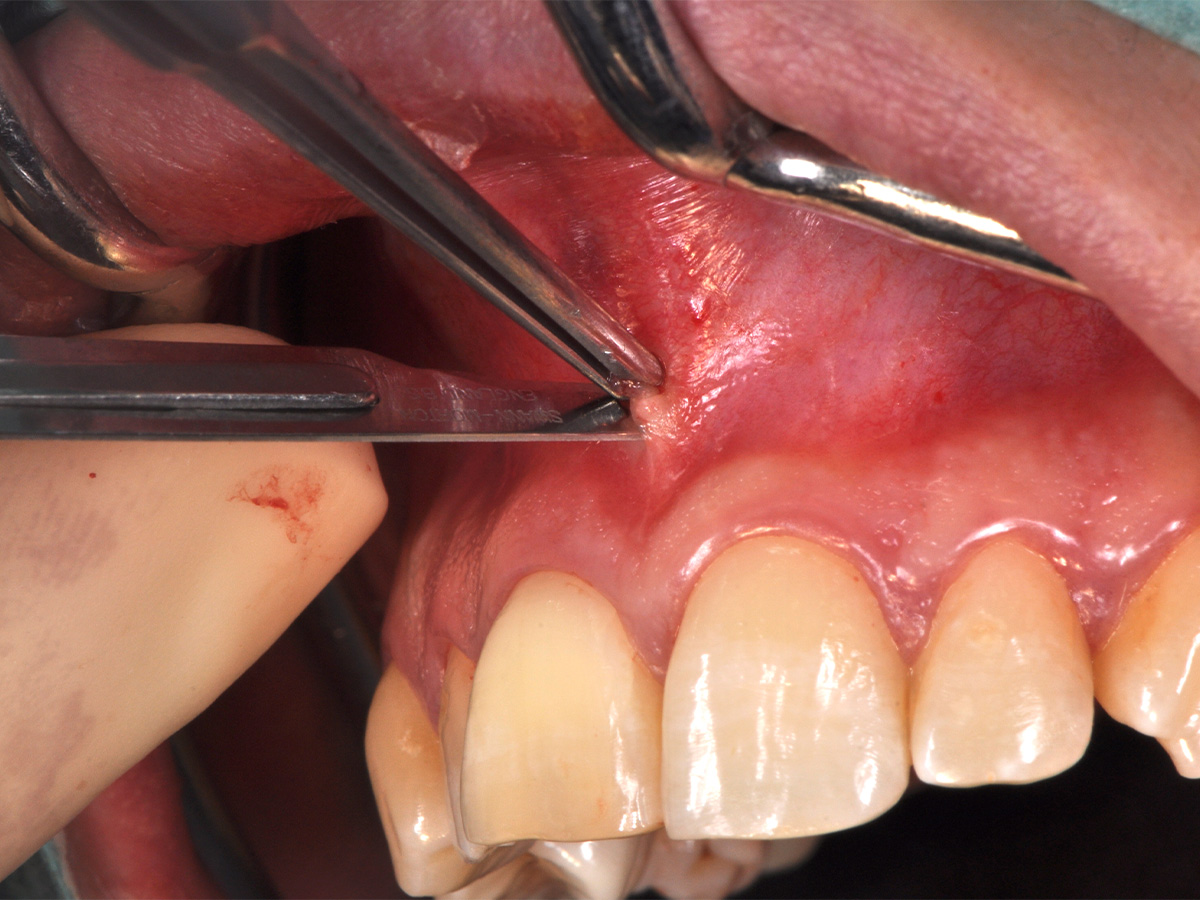

Abbildung 8

Die Schnittführung wurde aufgrund des bestehenden „Gummy Smile“ hoch im Vestibulum geführt...

Abbildung 9

...so konnte die delikate Parodontalstruktur in ihrer Form unangetastet belassen werden, um einen möglichst optimalen ästhetischen Erfolg zu erreichen.

Mit der Patientin wurde der Versuch des Zahnerhaltes trotz ausgedehnter Zyste besprochen. Gleichzeitig sollte das Zystenlumen zu einer sicheren ossären Durchbauung geführt werden, um eine implantologische Sofortversorgung vorzubereiten, falls zu einem späteren Zeitpunkt eine Zahnentfernung notwendig werden sollte. In der Phase vor der geplanten Operation wurden die Wurzelkanalfüllungen an Zahn 11 und 12 durch einen Endodontologen alio loco revidiert. Die Schnittführung wurde aufgrund des bestehenden „Gummy Smile“ hoch im Vestibulum geführt – so konnte die delikate Parodontalstruktur in ihrer Form unangetastet belassen werden, um einen möglichst optimalen ästhetischen Erfolg zu erreichen (Abb. 8, 9). Nach vestibulärer Freilegung wurde die Zyste vollständig entfernt und zur histopathologischen Untersuchung eingesandt (Abb. 10). Anschließend erfolgte eine Wurzelspitzenresektion an den Zähnen 11 und 12 durch die vestibuläre ossäre Perforation (Abb. 11), gefolgt von einer ultraschallbasierten, retrograden Kanalaufbereitung und Abdichtung mit MTA. Um die knöcherne Durchbauung am Boden der Zyste osteoinduktiv zu unterstützen, wurden mit Hilfe eines mechanischen Knochenschabers aus dem Bereich des rechten naso-palatinalen Pfeilers Knochenchips entnommen und als erste basale Augmentationsschicht in den ossären Defekt eingebracht (Abb. 12). Der größere Anteil von 80 % des Defektvolumens wurde mit einem vollständig resorbierbaren, xenogenen Augmentationsmaterial aufgefüllt (Abb. 13) (mp3®, OsteoBiol®). Der Defekt wurde zum Vestibulum hin mit einer stabilen, vollständig degradierbaren Membran abgedeckt (Abb. 14) (Soft Cortical Lamina, OsteoBiol®). Zum einen wurde hiermit im Sinne der GBR das Weichgewebe vom Augmentat getrennt. Zum anderen verhinderte die stabile Membran das Einwachsen eines Weichgewebeankers in den Defekt und damit eine narbige Verziehung im Vestibulum. Um eine Verschiebung der Membran zu vermeiden, wurde diese mit zwei Titanpins in der Kortikalis fixiert. Die Pins wurden bei Beschwerdefreiheit in situ belassen (Titan-Bone-Pin-System). Der Wundverschluss erfolgte einschichtig mit nicht resorbierbarem Nahtmaterial (Abb. 15) (Seralene® 5-0 DS-15). Peri- und postoperativ wurde eine antibiotische Abschirmung unter Fortführung für insgesamt drei Tage mit Amoxiclav 875/125 1-0-1 durchgeführt.